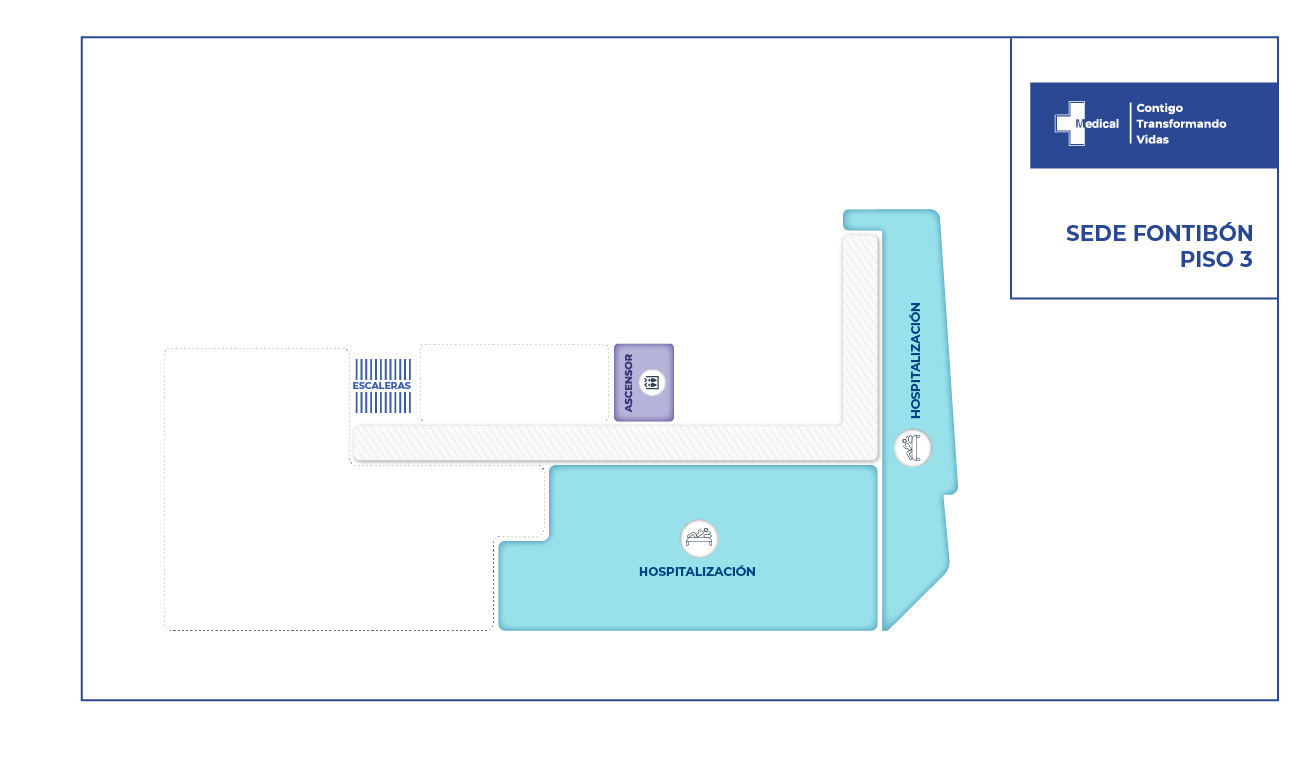

Desde el ingreso fue claro que el paciente no recobraría la movilidad de las piernas dada a la sección medular completa, sin embargo el equipo de especialistas intervino al paciente con la finalidad de evitar deformidad mayor en la columna vertebral, disminuir el riesgo de fracturas a otro nivel vertebral, adopción de una postura más estable, disminución de dolor. Todas ellas enfocadas en brindar al joven paciente una opción de mejorar su calidad de vida.

Nuestros resultados se obtienen gracias a la integralidad, oportunidad en los servicios, contamos con profesionales altamente especializados en este tipo de traumas, brindando al paciente y a su familia confianza y seguridad en los tratamientos instaurados.